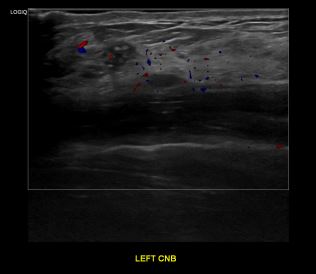

상기환자 외부검사이상으로 정밀검사위해 내원하신 40대 여성분으로

좌측유방 혹 총조직검사 시행해 유방암 진단되었습니다.